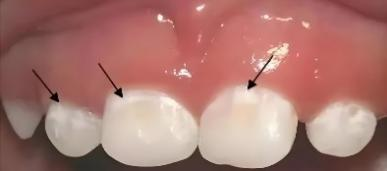

第一阶段(脱矿):细菌利用食物残渣(尤其是糖分)产生酸性物质,这些酸会慢慢腐蚀牙齿最外层的牙釉质。这个阶段,牙齿表面可能只是出现白色或褐色的斑点,但质地仍然完整,没有实际的“洞”。您通常没有任何感觉。